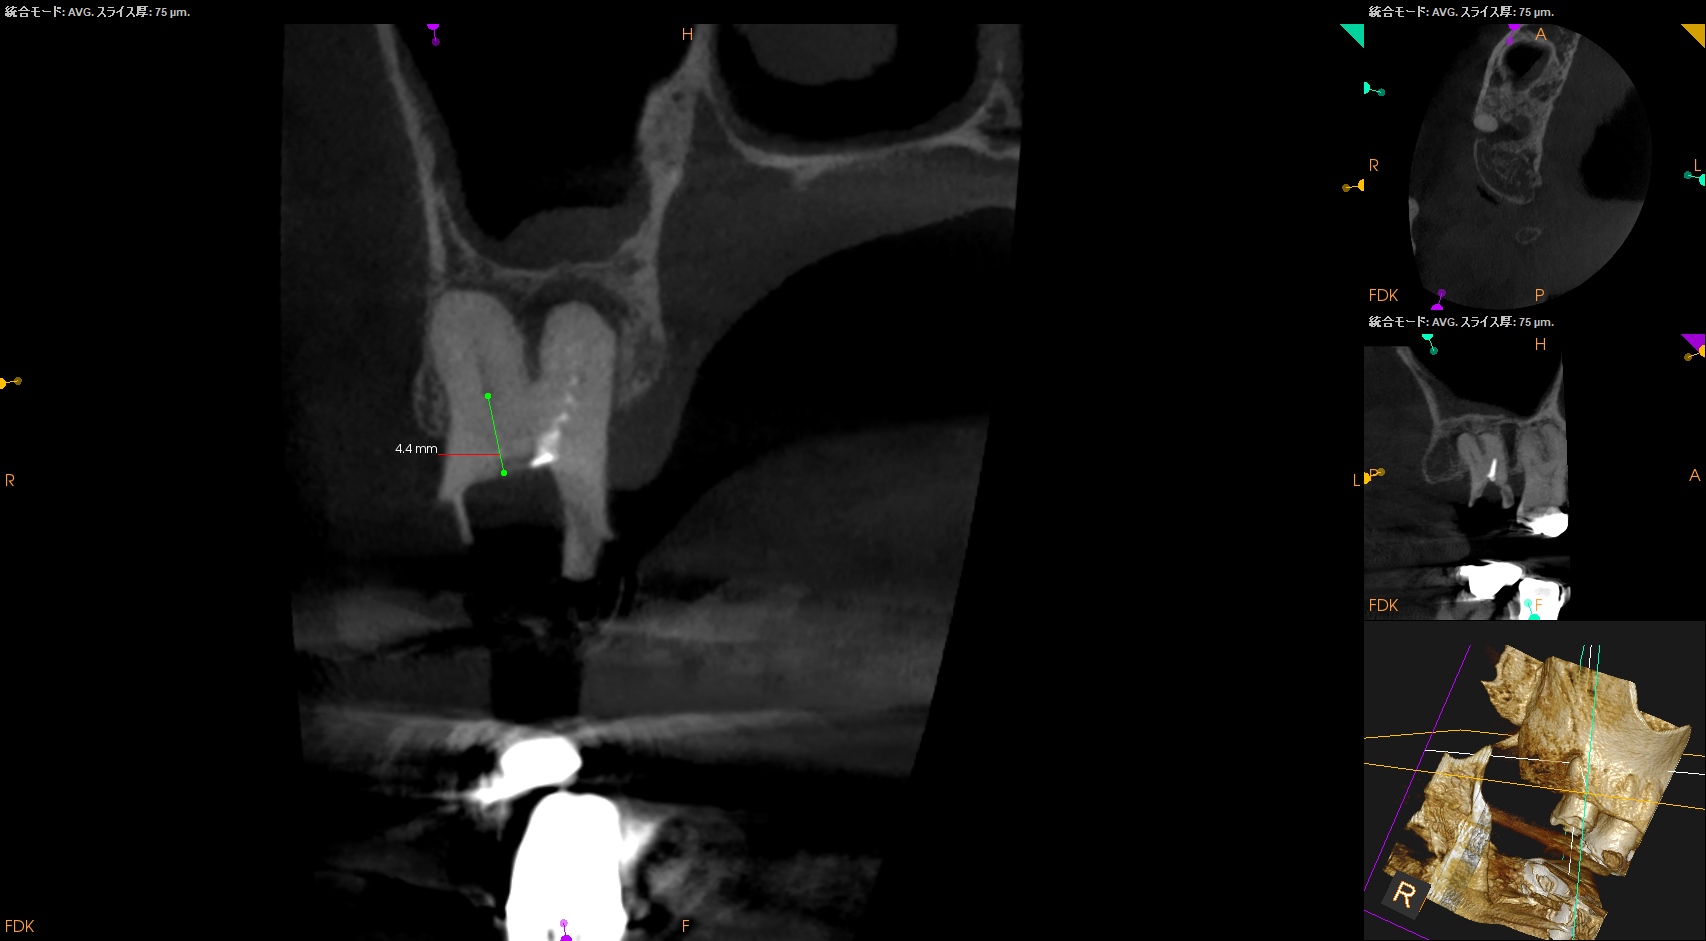

根尖病変があり頬側歯槽骨が穿孔しているDB, レンツロが破断しており根尖病変があるPをSelectiveに再根管治療するという方針を術前に決定した。

それの除去に没頭?すると時間を取られるのでまずはDBからだ。

が、根管口がどの辺りに存在するか?判然としない。

そこでMBのGutta Percha Pointを目印にDBを探索することにした。

SXで上部を拡大した後に根管形成した。

根管充填後にPA, CBCTを撮影した。

DB

P

問題はないだろう。